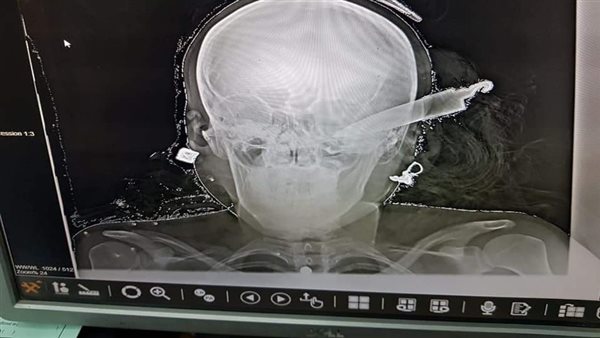

تمكن الفريق الطبي بمستشفى "شبين الكوم" التعليمي بمحافظة المنوفية، اليوم الثلاثاء، من إنقاذ حياة سيدة تعرضت لضربة بسلاح أبيض "سكين" في رأسها.

ونجح الفريق الطبي، برئاسة الدكتور إسلام العربي، وإشراف الدكتور محمد موسى، من استخراج السكين، فيما لا تزال السيدة تحت الملاحظة بالعناية المركزة بالمستشفى.